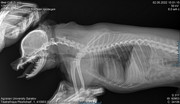

Коллапс трахеи форум